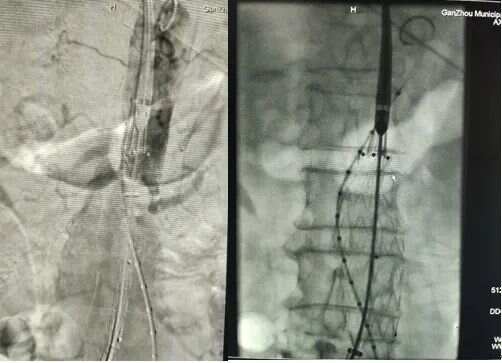

1.根據(jù)3D打印血管制定的手術(shù)方案,腹主動(dòng)脈血管造影,提示動(dòng)脈瘤位置及各血管分支情況。

2、為防止支架釋放后,髂外和髂內(nèi)動(dòng)脈匯合處產(chǎn)生內(nèi)瘺,提前將髂內(nèi)動(dòng)脈栓塞。

3、建立雙股動(dòng)脈通路;雙側(cè)導(dǎo)管交匯于腹主動(dòng)脈

4、根據(jù)3D打印血管模型輔助支架放置的位置。右股動(dòng)脈入路導(dǎo)入支架主體,分支導(dǎo)絲引出體外,腹主動(dòng)脈段部分釋放

5、造影調(diào)整支架位置,調(diào)整導(dǎo)絲纏繞問(wèn)題,注意左右腎動(dòng)脈的位置關(guān)系

6、造影明確后釋放支架主體;注意力度及方向

7.主體支架釋放后造影,左右髂動(dòng)脈分支通暢